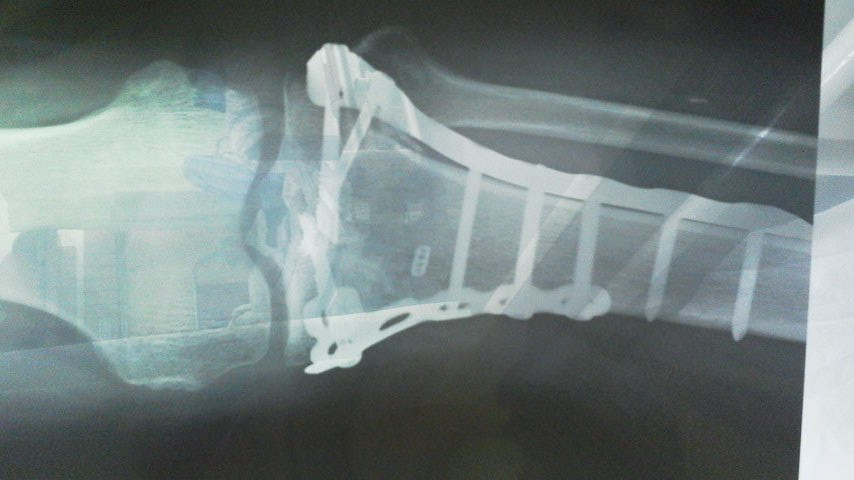

マーニも故障しますが 長い間には体も故障します。 当然オペが必要な場合もあります。 杉さんはマーニも膝も全快しましたが 両膝のオペをしました。そして左の膝は4分割に割れる開放骨折でしたから完治するまでに時間が掛かりました。

膝にプロテクターの入ったクシタニのパンツを穿いていましたが それでも充分ではない場合だってあります。  なので丈夫なプロテクターの装着は必要だなと思うのです。  オペや医療技術は間違いなく向上していますが感染症やその他のリスクを考えると事故などのトラブルは未然に防ぐ事ができればとても幸せです。

手術当時膝に入っていたチタン金具は両手に余る程の量、 金額が30万円ばかりと聞いたそうです。  医療器具なので高価なのですね。  今はこのような話が出来るまでに快復しましたが そうなるまでには誰しも時間が掛かります。

傷跡は かなり派手ですね、 骨折が酷かったので大きく切り開いたのでしょう。

今は医療技術が発達しているので このように再建する事が可能です。 物怖じせずに優秀な医療施設で治療すれば完治できる善い時代になりました。